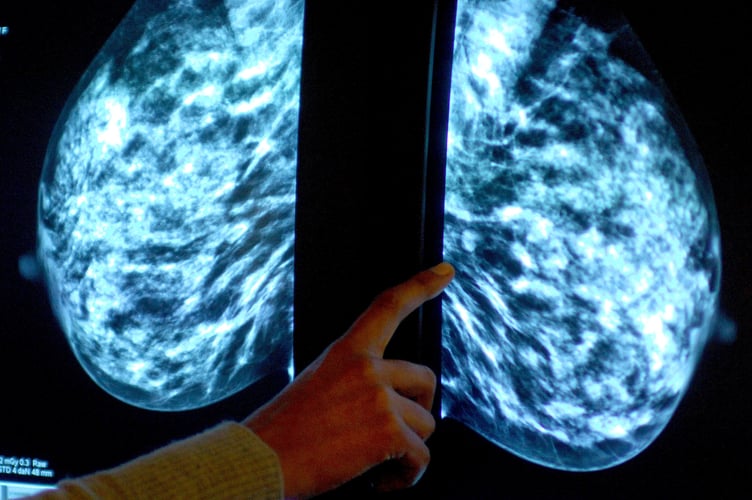

NHS England figures show 47,240 of the 72,250 people invited for a screening in the former NHS Devon CCG had a test in the year to March this year.

It meant uptake of the screening stood at 65% – down from 69% the year before, and below pre-pandemic levels of 74% in 2019-20.

The figures show breast screening uptake across England increased to 65% last year from 63% in 2021-22. However, it remained well below pre-pandemic levels when 70% was recorded.